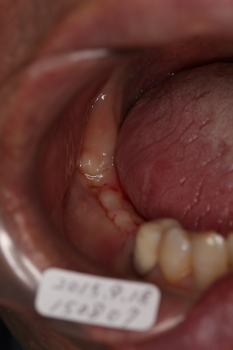

口腔内写真

麻酔後